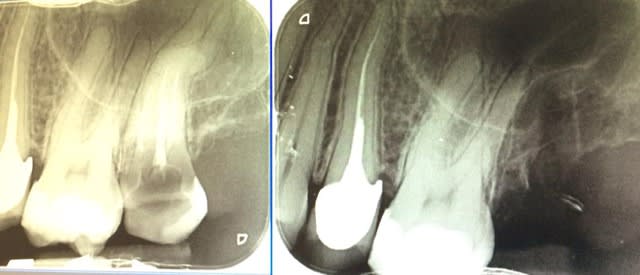

23/05/2015 à 17h17

transplant chez un jeune de 19 ans je crois

contrôle à 6 mois

Transplant 28 fvti6f - Eugenol

Loukoumparisien écrivait:

-------------------------

> transplant chez un jeune de 19 ans je crois

> contrôle à 6 mois

Énorme !!!!!! Bravo aussi .